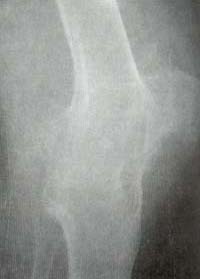

En el hombro se observa disminución regular del espacio articular y gran erosión superolateral en la tuberosidad mayor (signo del hachazo). La fusión glenohumeral es rara. En la rodilla se observa disminución del espacio articular uniforme con cambios óseos hipertróficos (Figura 10).

Figura 10. Rodilla. Cambios hipertróficos, anquilosis con formación de puentes óseos entre

el fémur y la tibia y entre patela y los anteriores.